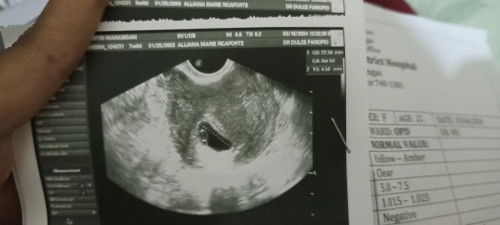

7weeks turning 8weeks base on last mens

Possible Po kaya Mali Ang bilang? Base Po kase sa tvs ko GA (Gestational age) 6weeks and 4days pero Ang count nila Ng weeks ko is base sa huling Araw Ng regla. I don't know if irregular ba Ang tawag. Nag stop Po kase ako mag depo last year May-June 2months Po ako Hindi dinatnan at ilang buwan din Po akong nag spotting nun (negative PT) Di Rin Po kase ako nireregla nun kahit na nag d-depo / injectable ako. Possibly Po kaya na Mali ung counting Ng weeks of pregnancy ko? Due of the side effects of depo and parang ngaun pa lang Po kase bumabalik sa normal Yung flow Nung menstruation ko (way back January my last menstruation

7weeks pregnant

Hello po, any opinion Po or same case. 4weeks-5weeks Po ata Nung nag first transv ako only Gestational sac lang Po Ang Nakita. Then yesterday Po is 7weeks na Po ako,may development Naman Po . Kaya lang Ang Nakita ay gestational sac at yolk sac. No heartbeat 😥 nag worry Po ako. Possible may kinalaman Po kaya ito sa pagka cs ko sa pangalawa ko,kase nababasa ko Po na Minsan consider sila sa high risk. Wala Naman Po ako nararamdaman na kakaiba. Spotting o anuman. Normal lang Po. At madalas Po ako antukin tuwing tanghali unlike dun sa 2 Kong anak base on experience na may dizziness at pagkapihikan sa pagkain (pagkakapoy) Dito Naman Po sa dinadala ko normal lang Po.